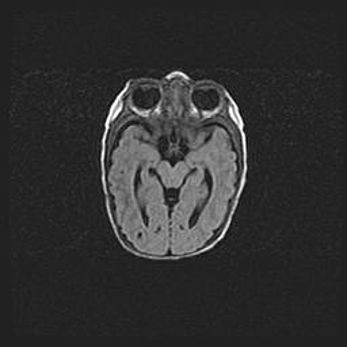

Церебральная ишемия II.

Возраст: 5 дней

Вес: 3400 г

Пол: женский

Окружность головы: 35 см

Срок гестации: 39 недель

Церебральная ишемия – это заболевание, характеризующееся недостаточностью (гипоксией) либо полным прекращением (аноксией) снабжения мозга кислородом по причине закупорки одного или нескольких сосудов. Это приводит к  что метаболическим расстройствам различной степени тяжести в тканях головного мозга, развитию коагуляционных некрозов и гибели нейронов.